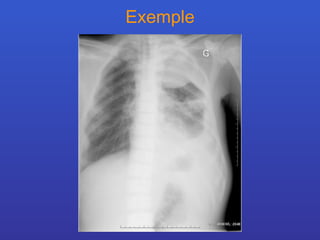

Exemple

Définition: Le syndrome alvéolaire se définit par une atteinte des espaces aériens distaux, au cœur du lobule pulmonaire. Critère  radiologiques répartition systématisée lobaire ou segmentaire limites floues tendance à la confluence bronchogramme et/ou alvéologramme aérique répartition en aile de papillon